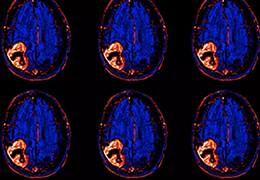

Eclipse 成像智能功能提供强大的处理能力和最佳质量的影像,同时减少质量错误并提高剂量效率。

凭借 AI、专有算法和先进的影像处理能力,提供出色的影像质量和无与伦比的诊断信心。

与标准影像处理相比,智能降噪功能可使客户降低辐射剂量,而不会损失影像质量。这在新生儿和儿科成像中尤其重要,在这种情况下以尽可能低的剂量成像至关重要。